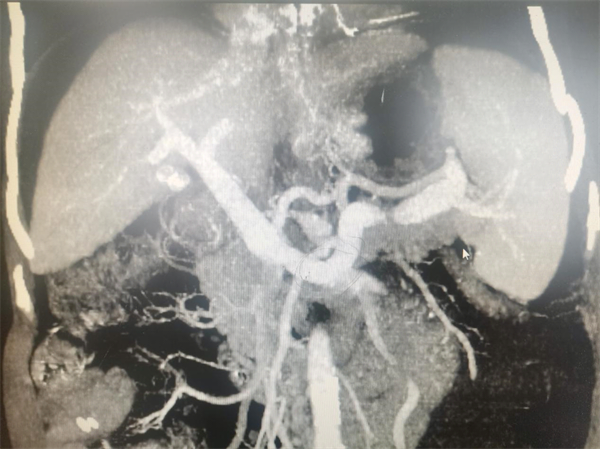

患者女,58岁,因“上腹胀痛3+天”入院,肝硬化病史多年,腹水反复发作。增强CT示:肝硬化、门静脉迂曲增粗、食管胃底静脉曲张、脾大、大量腹水。保守治疗(输注白蛋白、利尿、保肝等)效果欠佳,症状仍不能缓解。经普外科专家组讨论决定,予以实施TIPS手术。由犍为县人民医院硕士研究生、主治医师余鹏(主刀)和主治医师李杰(I助),于局部浸润麻醉下,用时2小时,顺利完成该术式。术后予以对症处理、监测生命体征等治疗措施,患者症状明显缓解,术后三日顺利出院。